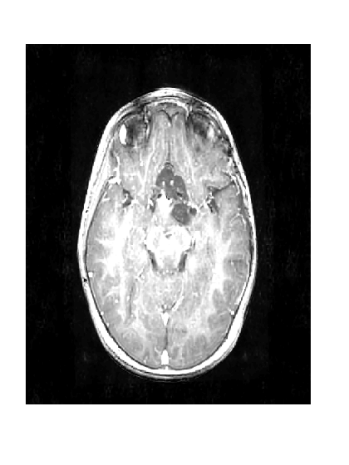

Figure 2: Image reconstruction from Case 20 (a, b, and c) and Case 3 (e, f, and g) of a brain image. Case 20 is the best performing algorithm that uses L1-W and case 3 is the best performing algorithm that uses LACS-MRI

The phantom image that we used in the previous experiment is flat and has less texture while the brain images has a lot of wrinkles and complex shapes. While the phantom image is small, the brain image is too large to calculate fNDsubscript𝑓𝑁𝐷f_{ND} efficiently. Thus, we conducted an experiment in the same setting as the phantom image excluding cases using fAsubscript𝑓𝐴f_{A}: cases 6 through 8 and 14 through 16. In this experiment, contrary to results for the phantom image experiment, L1-W performs better than LACS-MRI. For example, Case 3 performed the best among cases using LACS-MRI but it performs worse than 6 cases that use L1-W. Interestingly, one of the cases that shows an outstanding image recovery purely uses fVDSsubscript𝑓𝑉𝐷𝑆f_{VDS} with L1-W. However, purely using fVDsubscript𝑓𝑉𝐷f_{VD} with L1-W shows a dramatically worse performance. In conclusion, we are unsure why each combination of mixed PDFs and reconstruction algorithm perform differently based on the images processed, but this differing behavior is crucial to highlight for practical applications. We conjecture that the texture of the image is one factor that decides the performance of each algorithm. In the future, we may explore this conjecture and analyze why this happens.